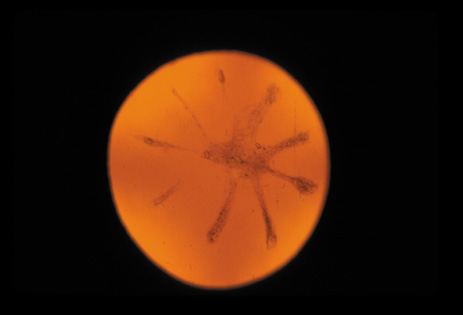

One can examine this type of cataract with direct illumination, using the narrow and broad beams of the slit-lamp to show the characteristic granular inner surface immediately in front of the posterior capsule (Fig. 13). The problem with this technique, however, is that patients may not tolerate any prolonged direct illumination because of the glare. Retroillumination is therefore more useful for revealing the outline of the opacity, since it is usually seen as an “island” in the center of the posterior capsule, which is further highlighted by the shadow cast by the opacities.33 However, in the early stages of this type of cataract, the dust-like particles that might be noticeable in the central posterior subcapsular area with direct illumination disappear or are difficult to see with retroillumination (Fig. 14). Eventually this “dusting” becomes dense enough to cast a shadow and thus appear on retroillumination. The smooth orange background of the fundus helps to highlight the rough, irregular pseudopodia-like edges of the central opacity. In advanced stages, the PSC may become a thick, calcified plaque (Fig. 15). During surgery, excessively vigorous scraping or vacuuming of the calcified opacity can lead to rupture of the posterior capsule. Usually, small remnants that are left behind after surgery are reabsorbed and do not interfere with vision; otherwise, they are easily treated with a neodymium : yttrium (Nd:YAG) aluminum garnet laser. Pathologic evidence suggests that most PSCs result from the migration of bow region cells into the potential space (along with accumulated cellular debris) between the posterior capsule and the cortex.34–36

Fig. 13. Direct slit-lamp illumination of a PSC, showing an irregular granular surface in front of the posterior capsule.

Fig. 14. A PSC, showing vacuoles and dust-like material in the potential space between the posterior cortex and the capsule.